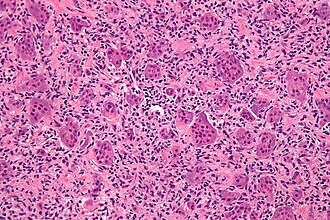

Giant cell tumour of bone. H&E stain. | |

| LM | giant cells (usu. with >10 in the plane of section), mononuclear cells and small multinucleated cells with nuclei similar to those in the giant cells |

- Giant cells with a large number of nuclei (usu. >10 in the plane of section).

- Usu. have prominent nucleoli.

- Mononuclear cells and small multinucleated cells with nuclei similar to those in the giant cells - key feature.

- +/-Hemosiderin deposition - not common.[4][5]

- Giant cells typically present in abundance.